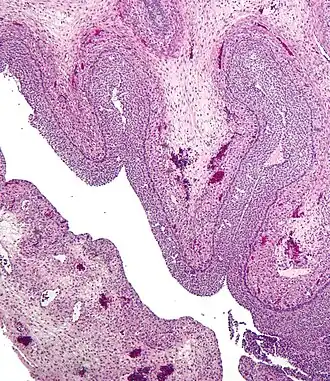

Section of the ovary. 1. Outer covering. 1’. Attached border. 2. Central stroma. 3. Peripheral stroma. 4. Bloodvessels. 5. Vesicular follicles in their earliest stage. 6, 7, 8. More advanced follicles. 9. An almost mature follicle. 9’. Follicle from which the ovum has escaped. 10. Corpus luteum.

The corpus luteum (Latin for "yellow body"; pl.: corpora lutea) is a temporary endocrine structure in female ovaries involved in the production of relatively high levels of progesterone, and moderate levels of estradiol, and inhibin A.[1][2] It is the remains of the ovarian follicle that has released a mature ovum during a previous ovulation.[3]

Development and structure

The corpus luteum develops from an ovarian follicle during the luteal phase of the menstrual cycle or oestrous cycle, following the release of a secondary oocyte from the follicle during ovulation. The follicle first forms a corpus hemorrhagicum before it becomes a corpus luteum, but the term refers to the visible collection of blood, left after rupture of the follicle, that secretes progesterone. While the oocyte (later the zygote if fertilization occurs) traverses the fallopian tube into the uterus, the corpus luteum remains in the ovary.

The corpus luteum is typically very large relative to the size of the ovary; in humans, the size of the structure ranges from under 2 cm to 5 cm in diameter.[4]

Its cells develop from the follicular cells surrounding the ovarian follicle.[5] The follicular theca cells luteinize into small luteal cells (thecal-lutein cells) and follicular granulosa cells luteinize into large luteal cells (granulosal-lutein cells) forming the corpus luteum. Progesterone is synthesized from cholesterol by both the large and small luteal cells upon luteal maturation. Cholesterol-LDL complexes bind to receptors on the plasma membrane of luteal cells and are internalized. Cholesterol is released and stored within the cell as cholesterol ester. LDL is recycled for further cholesterol transport. Large luteal cells produce more progesterone due to uninhibited/basal levels of protein kinase A (PKA) activity within the cell. Small luteal cells have LH receptors that regulate PKA activity within the cell. PKA actively phosphorylates steroidogenic acute regulatory protein (StAR) and translocator protein to transport cholesterol from the outer mitochondrial membrane to the inner mitochondrial membrane.[6]